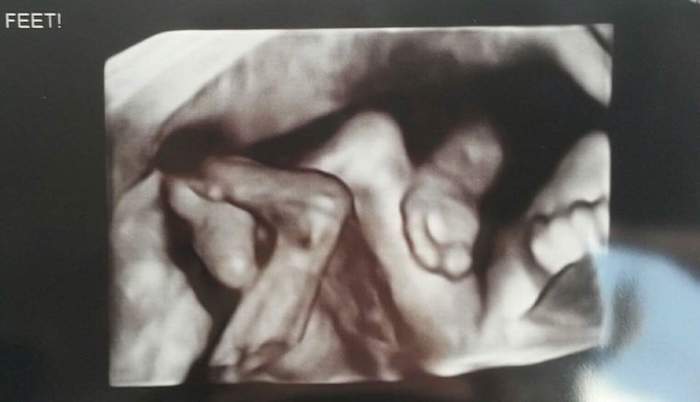

Ultrasound Photos at 21 Weeks Pregnant With Twins